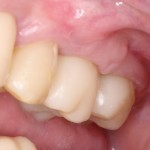

Имплантация и остеопластика: вместе или врозь? Часть II плюс Ankylos, плюс Geistlich